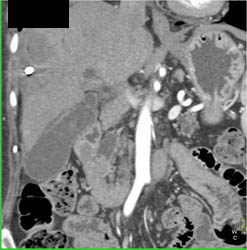

Subtle Islet Cell Tumor of the Pancreatic Head